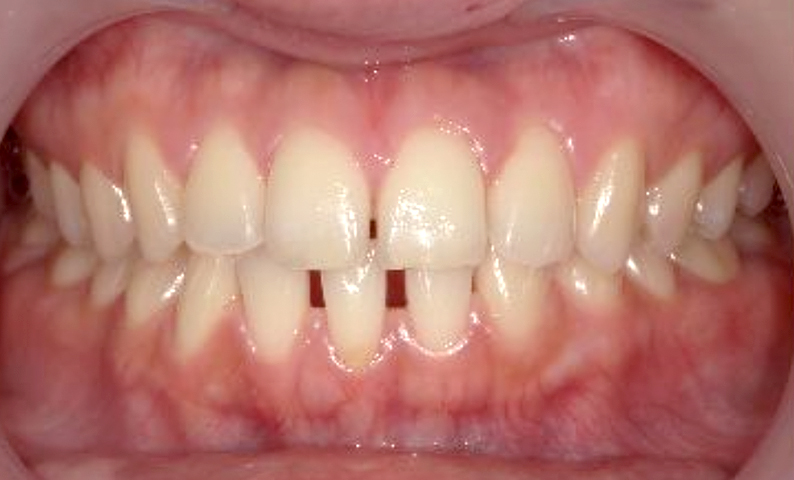

| 治療前 | 治療後 |

|---|---|

|